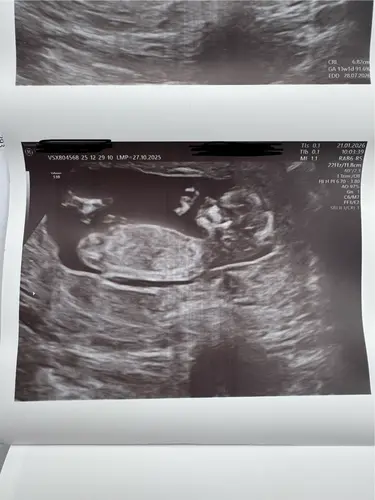

Vandaag de 12 weken echo laten doen! Ons spruitje meet 6,82cm. Nu de nipt spannend afwachten ahhh 🤭 neusbeentje is aanwezig en ook de nekplooi zag er oke uit dus we zijn weer even gerustgesteld 🥹

Vandaag exact 12w! 🤩